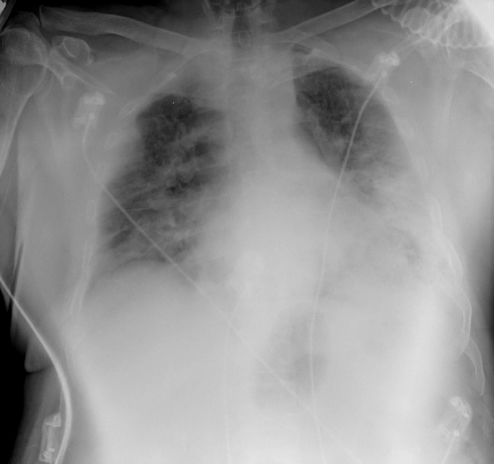

急诊部检查:患者有肋间凹陷、呼吸机过度使用等呼吸窘迫综合征表现;呼吸频率为34 次/分,给予面罩吸氧前氧饱和度为72%, 面罩吸氧(10 L/min)后达到96%;血压为111/72 mm Hg, 心率为91 次/分, 体温为36.8 ℃;无下肢水肿、颈静脉扩张, 心脏听诊无异常;肺部听诊示:双肺满布哮鸣音,胸部左下区闻及细湿罗音。实验室检查示:白细胞计数为6,290/mm3(9%肥大细胞和1%晚幼粒细胞), 血红蛋白为16.1 g/dL,血小板计数为94,000/mm3, CRP为192 mg/L。胸片提示:双侧肺间质浸润影,左肺下叶可见实变影(见图1)。

图1 正位胸片显示双侧肺间质浸润影, 左肺下叶可见实变影